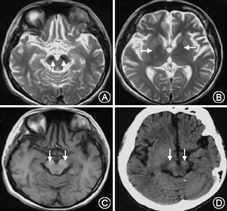

影像学特点:BPAN有两个特征性的影像学表现:(1)不同于以苍白球为铁沉积最明显部位的其他NBIA亚型,黑质部位是BPAN患者铁沉积最早和受累程度最严重的部位,苍白球也可累及(图2A,图2B);(2)其他NBIA亚型中铁沉积在T1像上往往表现为中等信号,但是在BPAN患者,T1像上为双侧黑质高信号伴或不伴有中央T1低信号带(图2C),T1像高信号有可能是由于铁与黑质部位多巴胺能神经元死亡释放出的神经黑色素结合导致。此外,CT上双侧黑质可显示高密度影(图2D),提示可能存在继发性的钙沉积。